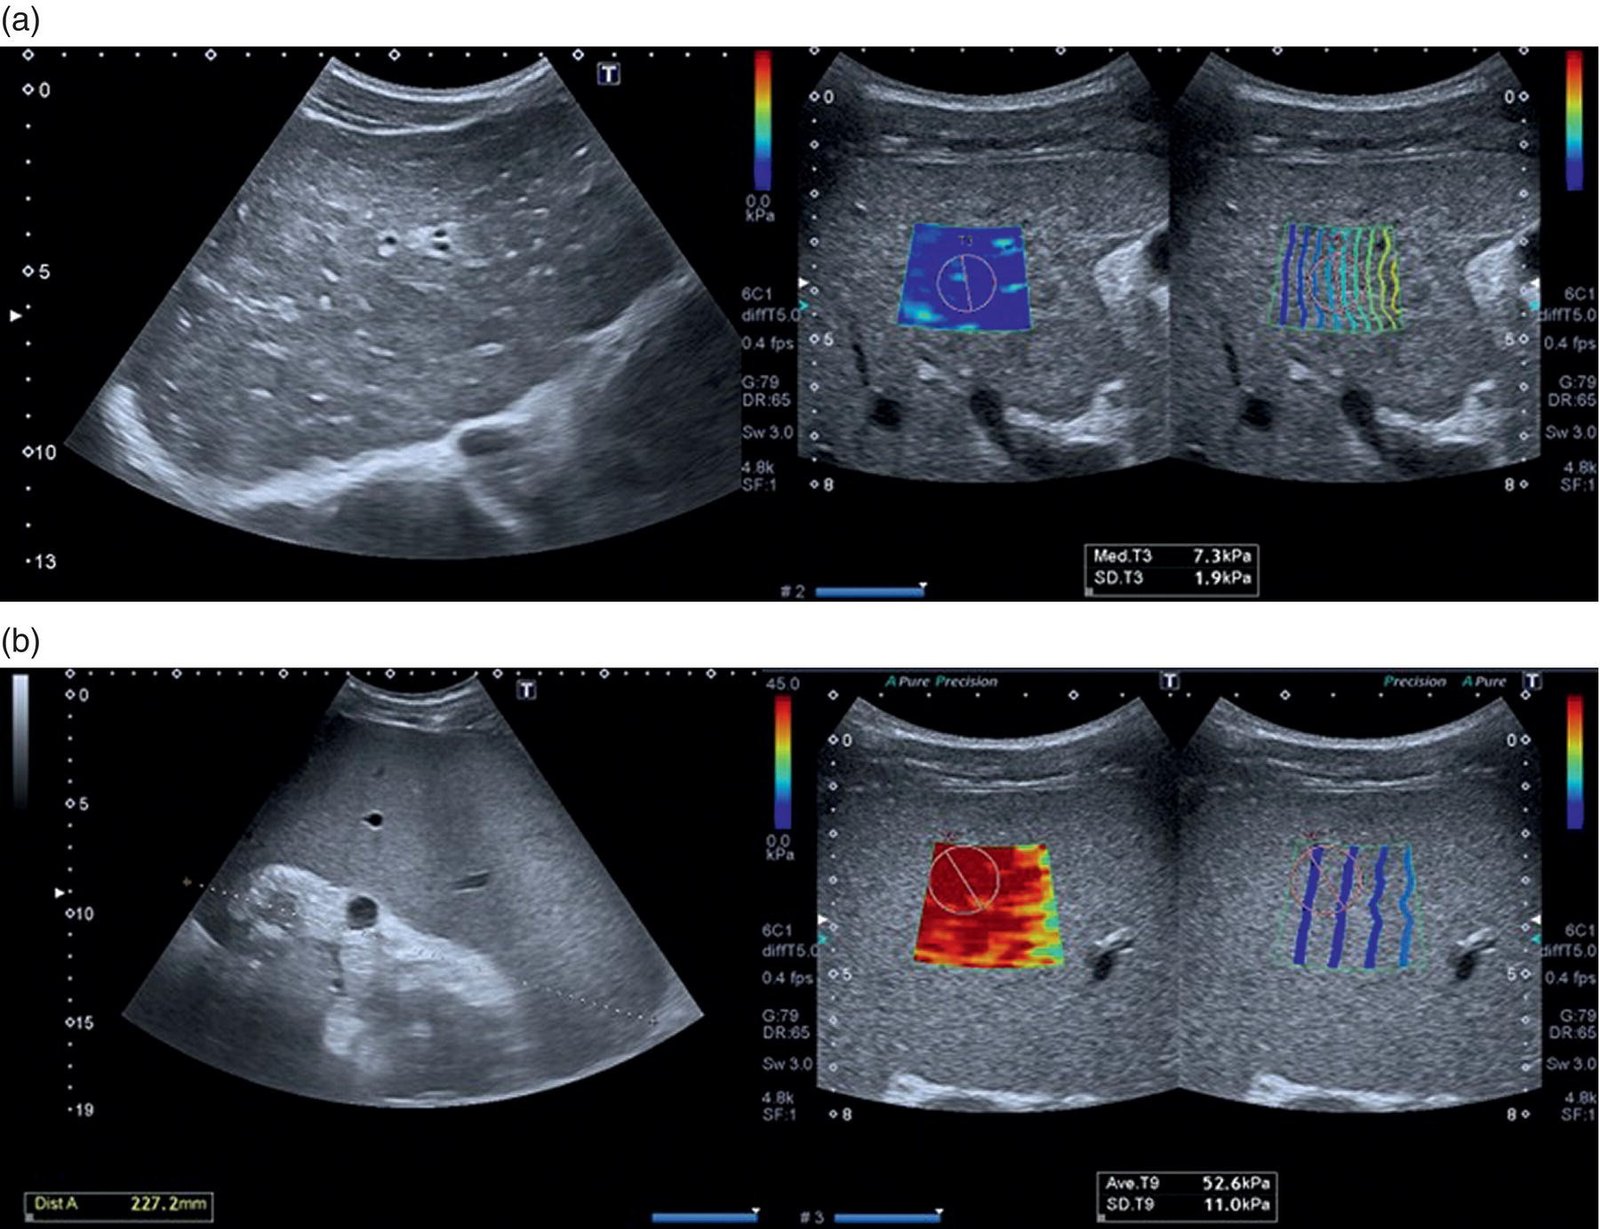

At Indianova Heart Center and Diagnostics, we provide Elastography, an advanced ultrasound-based imaging technique that measures the stiffness or elasticity of tissues. Unlike conventional ultrasound, which shows the structure of organs, elastography provides additional information about tissue properties, helping doctors detect abnormalities with greater accuracy.

This technique is especially valuable in the early detection and monitoring of conditions such as liver fibrosis, breast lesions, thyroid nodules, and other soft tissue abnormalities. By offering a non-invasive alternative to biopsy in many cases, elastography allows patients to receive quicker, safer, and more reliable diagnostic insights.